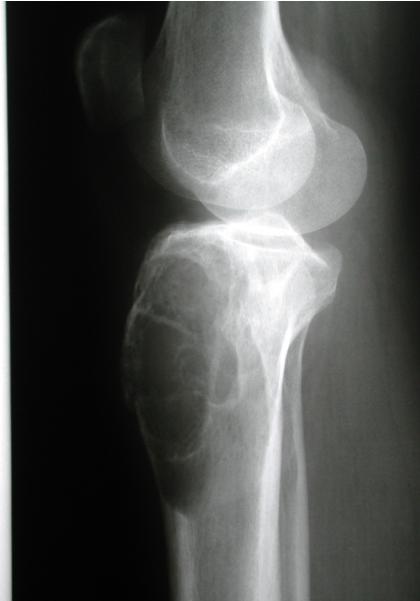

Other Diaphyseal Lesions

Could be malignant, even though no periosteal reaction, may be due old fracture

Pathological fracture, after metastasis